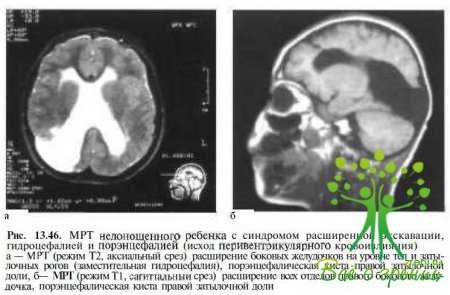

При НСГ, КТ и МРТ у 41 % детей с синдромом «расширенной экскавации» отмечается перивентрикулярная лейкомаляция (см. рис.13. 43, б, в), у 46 % — вентрикуломегалия, порэнцефалия или кистозная дегенерация вещества мозга в проекции задних зрительных путей и/или первичной зрительной коры, обусловленные внутриутробными энцефалитами различной этиологии, гипоксическими, геморрагическими и токсическими осложнениями, у 13 % — мальформации головного мозга (арахноидальные кисты, шизэнцефалия, голопрозэнцефалия, гидранэнцефалия).

Нейрорадиологические исследования и НСГ. У детей с синдромом расширенной экскавации и поражениями ЦНС гигюксически-ишемической этиологии, родившихся до 34-й недели гестации, преобладают изменения, вовлекающие зрительную лучистость, — дилатация тел, нижних и/или затылочных рогов боковых желудочков, сочетающаяся в ряде случаев с порэнцефалическими кистами Эти изменения выявляют обычно у недоношенных детей Преимущественное поражение перивентрикулярных структур у недоношенных детей обусловлено частым развитием перивентрикулярной лейкомаляции (рис 13.43, б), а также субэпендимальными и перивентрикулярными кровоизлияниями, источником которых является герминтативный матрикс (рис 13.45).

Локализация изменений в области затылочных рогов боковых желудочков объясняется неравномерной регрессией герминатипного матрикса, инволюция которого происходит вначале в области IV и Ш желудочков, а затем в области затылочных рогов боковых желудочков. Позднее у этих младенцев нередко развивается гидроцефалия (рис 13.46), при которой происходит поражение зрительных путей вследствие компрессии расширяющейся желудочковой системой, ишемических нарушений, а также деструктивных и атрофических процессов (например, у пациентов с так называемой гидроцефалией ex vacuo, при которой не происходит повышения внутричерепного давления).